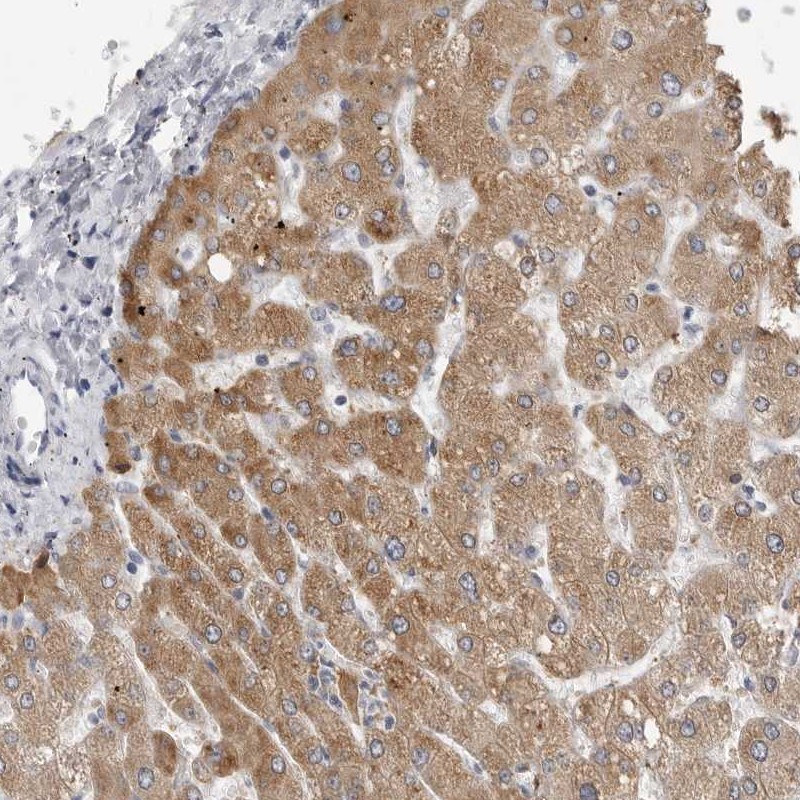

Immunohistochemical staining of human liver shows cytoplasmic positivity in hepatocytes.